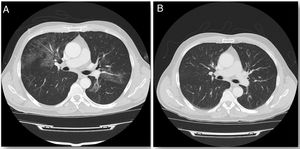

Comenzó terapia con GM-CSF inhalado siguiendo la pauta de administración empleada en el estudio de Tazawa et al.2, inicialmente a alta dosis (125 μg dos veces al día del primer al octavo día y descanso de noveno al décimo cuarto) durante seis ciclos de dos semanas, seguido de administración a baja dosis (125 μg una vez al día del primer al cuarto día con descanso del quinto al décimo cuarto) durante seis ciclos de dos semanas. Al finalizar el tratamiento mejoró la disnea y la tos, con mínima expectoración. A los dos meses la tomografía computarizada de tórax evidenció la desaparición completa de los infiltrados (imagen 1), junto con normalización de la DLCOc (82%) que se mantiene hasta la actualidad.